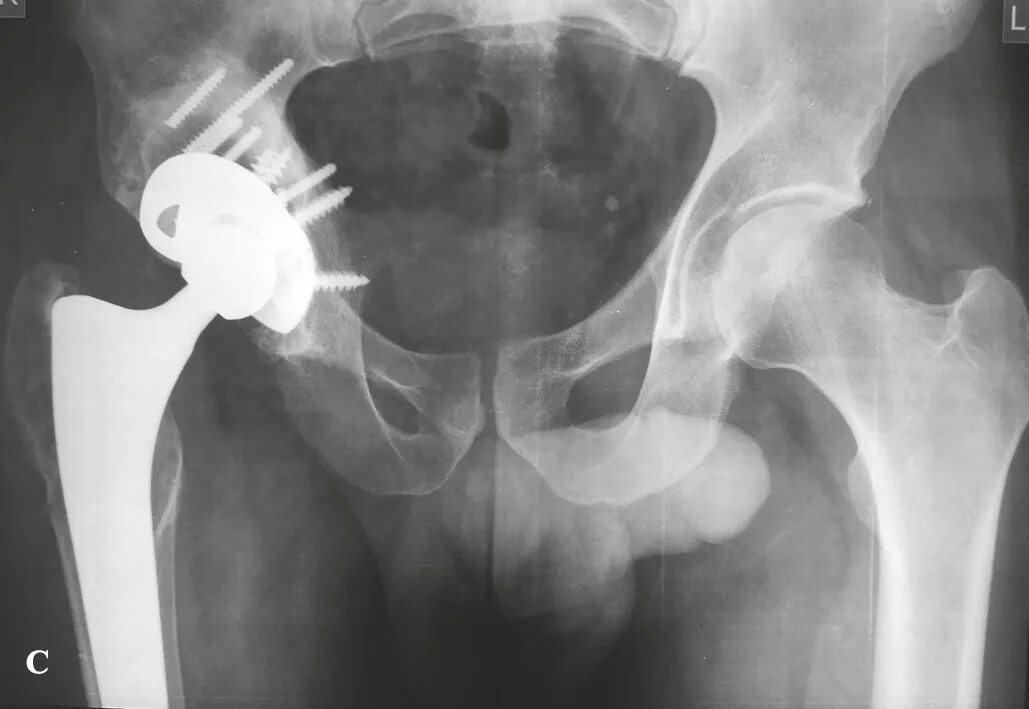

Ревизия тазобедренного сустава